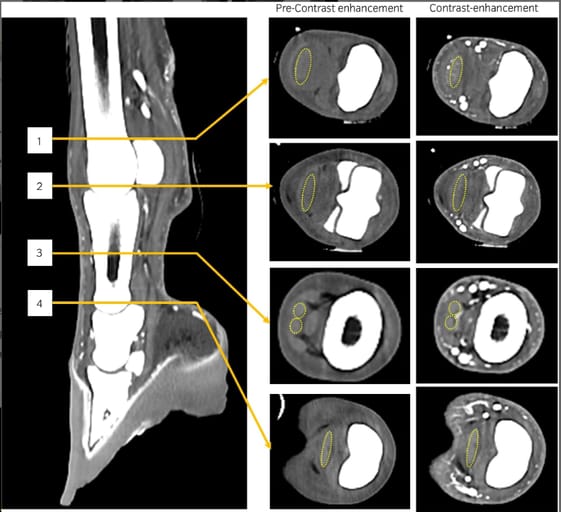

Six healthy Jeju horses underwent 54 intra-arterial CECT scans under general anesthesia. The first phase evaluated CE based on CM concentration (90–150 mg I/mL) and CT voltage (80 vs. 120 kV) using 50 mL contrast at 2 mL/s. The second phase explored combinations of CM volume (50–150 mL), rate (2–6 mL/s), and iodine delivery rate (IDR: 180 or 300 mg I/s), keeping total iodine dose constant. Hounsfield units (HU) were measured in the DDFT and medial/lateral palmar veins at four anatomical sites. CTDIvol, injector pressure, and anesthesia time were recorded.

Contrast enhancement of the DDFT was significantly higher at 80 kV with 150 mg I/mL CM (p < 0.05), showing a strong positive correlation with CM concentration (r = 0.75). Under fixed IDR (300 mg I/s), increasing CM volume or rate decreased DDFT enhancement but increased vein enhancement. At lower IDR (180 mg I/s), all enhancement metrics dropped significantly, particularly in groups using 30 mg I/mL CM. A CE of >900 HU was adequate to distinguish veins from surrounding structures. Most horses tolerated intra-arterial injections well, though one artery rupture was observed after high-pressure injection.

Measurements of Hounsfield unit (HU) of the deep digital flexor tendon (DDFT; yellow dash line) at four sites: (1) proximal margin of the proximal sesamoid bone; (2) distal margin of the proximal sesamoid bone; (3) mid-level of the proximal phalangeal bone; and (4) level of the proximal phalangeal joint.